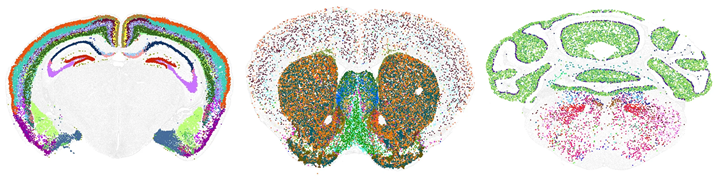

Atlas tế bào cơ thể người: Kỷ nguyên mới trong y học

Các nỗ lực mới nhất nhằm thiết lập bản đồ chi tiết từng tế bào trong cơ thể người, trước tiên là xây dựng bản đồ não người, đã cho thấy sự đa dạng đến kinh ngạc trong các tế bào cơ thể người. Chỉ riêng bộ não đã chứa…